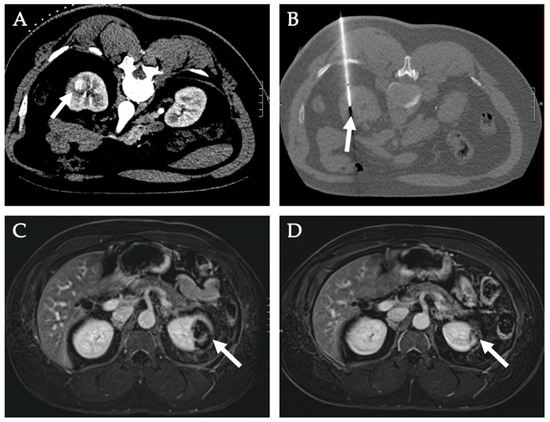

5. Renal Tumors

- Mauri, G.; Nicosia, L.; Varano, G.M.; Bonomo, G.; Della Vigna, P.; Monfardini, L.; Orsi, F. Tips and tricks for a safe and effective image-guided percutaneous renal tumour ablation. Insights Imaging 2017, 8, 357–363. [Google Scholar] [CrossRef] [Green Version]

- Samadi, K.; Arellano, R.S. Ureteral protection during microwave ablation of renal cell carcinoma: Combined use of pyeloperfusion and hydrodissection. Diagn. Interv. Radiol. 2018, 24, 388–391. [Google Scholar] [CrossRef]